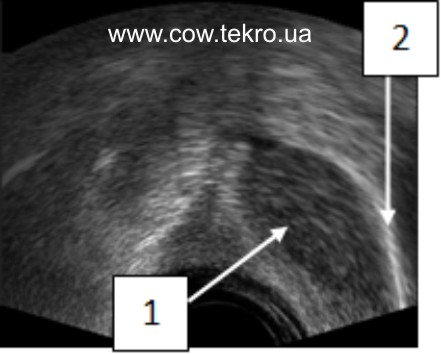

За ультразвукового дослідження у яєчниках візуалізується неоднорідна ехоструктура тканин, ущільнення кіркового шару гонад у вигляді ехопозитивної ділянки, без везикулярних фолікулів і жовтих тіл (рис. 4).

Рисунок 4 – Ехограма яєчника за гіпотрофії: 1 – тканини яєчника; 2 – ехопозитивна ділянка.